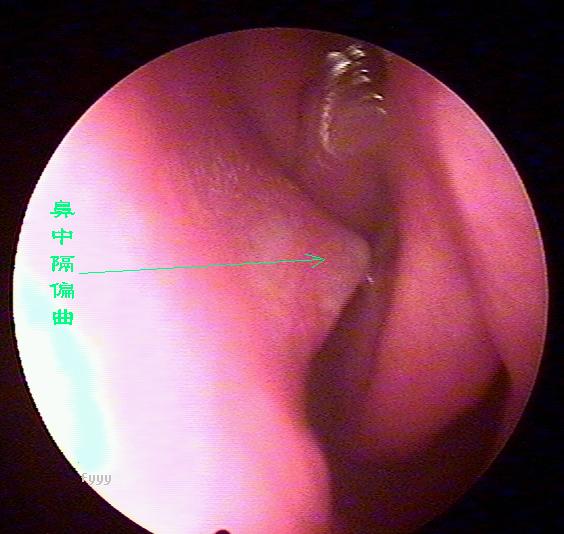

鼻内窥镜下的鼻中隔偏曲

鼻中隔偏曲进行鼻内检查以判断鼻中隔偏曲的类型和程度,注意鉴别鼻中隔粘膜肥厚和是否同时存在鼻内其它疾病,如原发病变—肿瘤、异物或继发病变—鼻窦炎、息肉等。 另一罕见者为鼻中隔梅毒瘤,其质地中亦较硬,但该处粘膜明显充血。